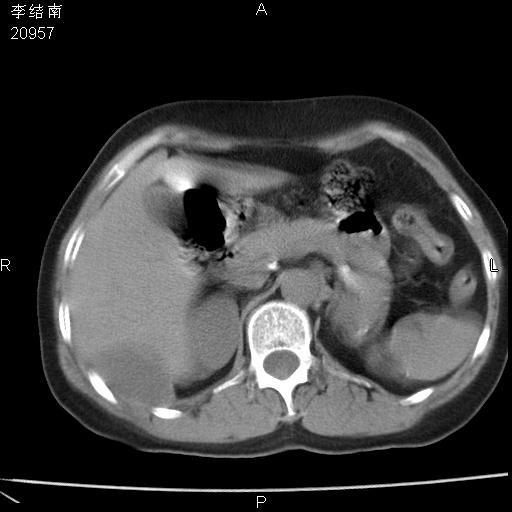

患者女,45岁,以右侧腰部包块来就诊,局部有压痛,皮肤颜色正常。因为是熟人扫的范围较大,患者有胆结石,胆源性胰腺炎病史。请大家看看,有手术病理。

胰尾部占位,伴腹膜后转移。

可能大家觉得片子的质量不好,当时是做下腹部扫描,所以没有常规喝水,右腹壁的病灶当时是,密度不均有钙化影,局部骨质没见破坏,肝脏应该是受压的表现,所以当时考虑为腹壁的良性占位,各位老师考虑的神经源性肿瘤,我当时还真没想到,胰腺是胰腺炎治疗后改变.膈脚旁的混杂密度包快不好考虑什么,到上级医院做增强(腹部)+肺部平扫后,发现腹壁的病灶呈不均匀性强化局部可见囊性灶,当时考虑为腹壁结核,最具戏剧性的是膈脚旁的混杂密度灶确是胃的一部分,而腹壁的病灶确是脂肪瘤(简直不可思议)但是我亲眼所见在我们县医院开的.

很不好意思 ,患者后来手术切口裂开,临床医生作了病理证实是腹壁结核。

[病理诊断] CT13183腹壁结核!